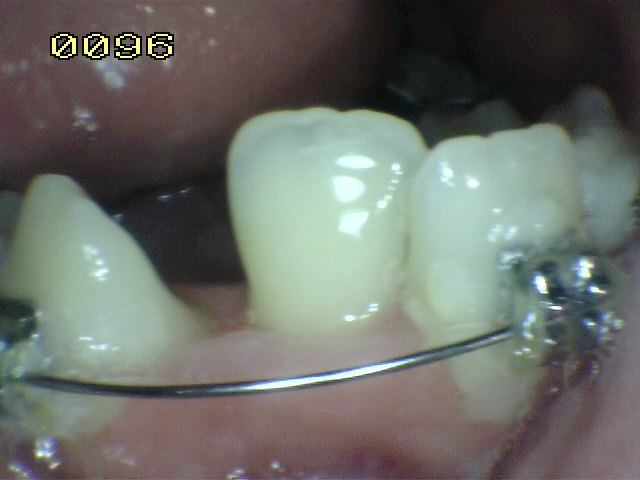

Observe el remanente de esmalte en la ángulo axio gingival

de la cavidad y la desadaptación de la matriz metálica |